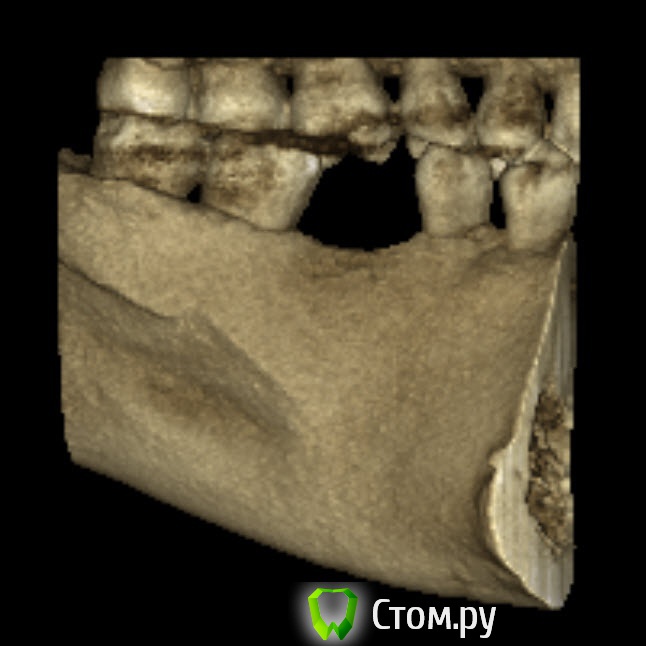

bobrdobr Опубликовано 18 февраля, 2014 Автор Поделиться Опубликовано 18 февраля, 2014 (изменено) Имплант был предложен Semados 4,1*11,5 без костной пластики. судя по фото, скорее всего нужна. От КТ нужен срез горизонтальной плоскости - вид сверху на костный гребень, на 1 мм ниже его вершины. Сейчас попробую. Прикладываю 4 снимка: на уровне гребня (как мне кажется) и на 1,2,3 и мм. ниже. Изменено 18 февраля, 2014 пользователем bobrdobr Ссылка на комментарий

Bier Опубликовано 18 февраля, 2014 Поделиться Опубликовано 18 февраля, 2014 Можно поставить, одновременно добавив немного кости и закрыть мембраной. Кость можно даже взять прямо из того места, куда будет ставиться имплантат, т.е. доп травмы не будет Ссылка на комментарий

bobrdobr Опубликовано 18 февраля, 2014 Автор Поделиться Опубликовано 18 февраля, 2014 Можно поставить, одновременно добавив немного кости и закрыть мембраной. Кость можно даже взять прямо из того места, куда будет ставиться имплантат, т.е. доп травмы не будетБольшое спасибо за мнение! Ровно такой вариант предлагал хирург 3 под винтовой имплант. Правда, он же предложил байкон Что будет, если кость не подсыпать и мембрану не ставить? Ссылка на комментарий

Bier Опубликовано 18 февраля, 2014 Поделиться Опубликовано 18 февраля, 2014 Может и ничего не будет, если широкий диаметр не выбирать и десну подсадить, а может десна немного отойдет вниз через годик-другой. Ссылка на комментарий

bobrdobr Опубликовано 18 февраля, 2014 Автор Поделиться Опубликовано 18 февраля, 2014 Все ясно, благодарю. Диаметр 4,1 мм предлагают (Semados). Нормально для жевательного зуба? Ссылка на комментарий

Bier Опубликовано 18 февраля, 2014 Поделиться Опубликовано 18 февраля, 2014 Тогда подсыпать однозначно нужно, 4,1- стандартная платформа. Лучше сюда ставить тонкую платформу. Неважно какой зуб, они держат нагрузку. Главное чтобы кость была вокруг имплантата. Ссылка на комментарий